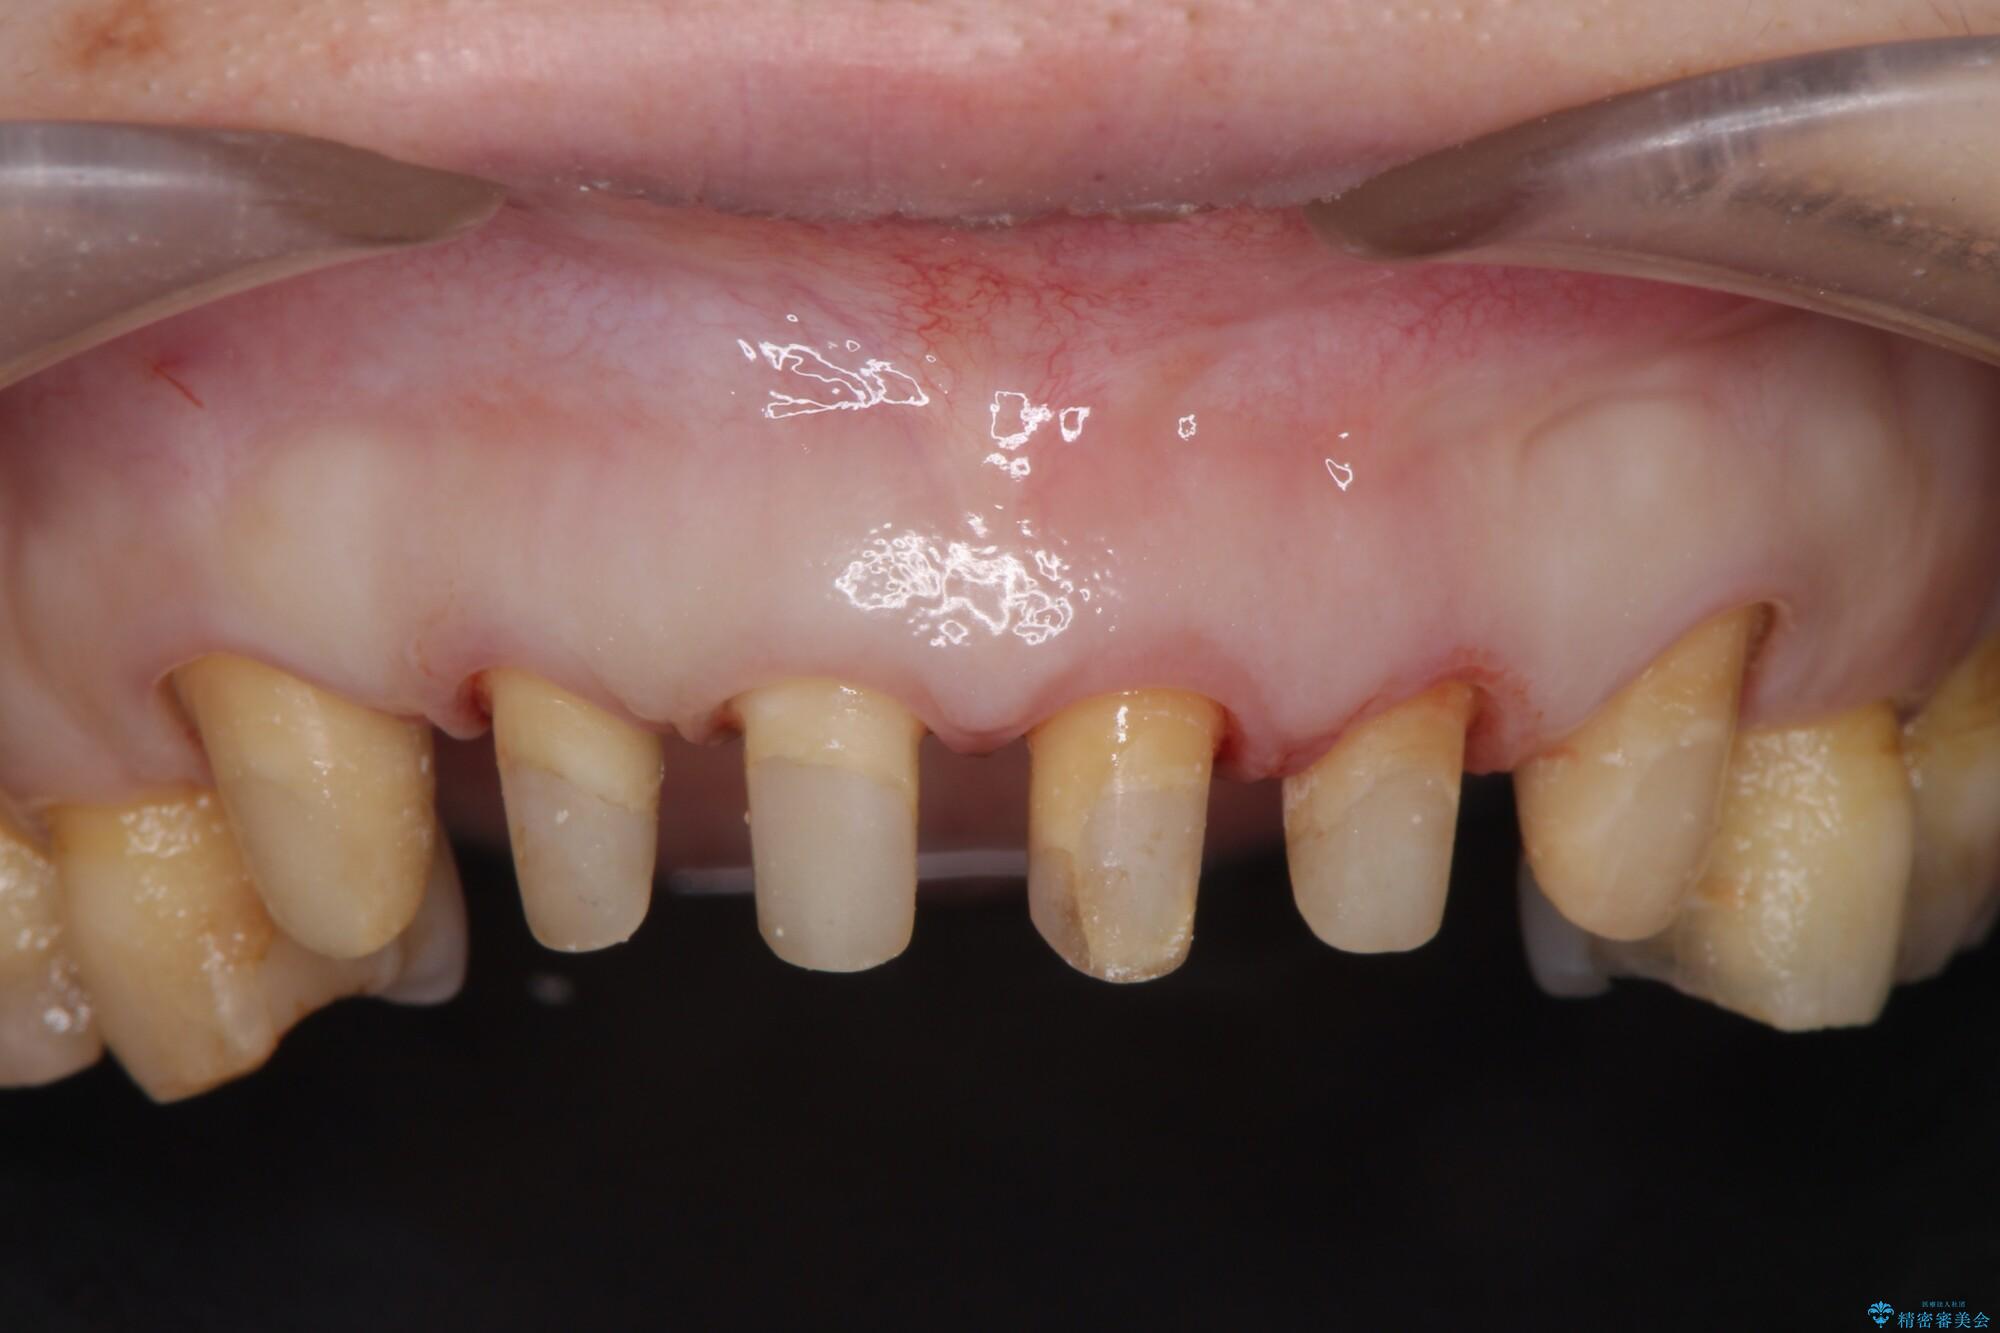

装着されていたセラミックを除去したところ、歯ぐきの奥深くまで歯牙は削られ、歯ぐきの炎症・出血が著しくみられる状態でした。

この状態で再度セラミッククラウンの作製・装着を行ってもまた同じ状態となってしまうため、歯周外科を行い歯ぐきの状態を整備したのちセラミッククラウン治療をおこなっていきます。